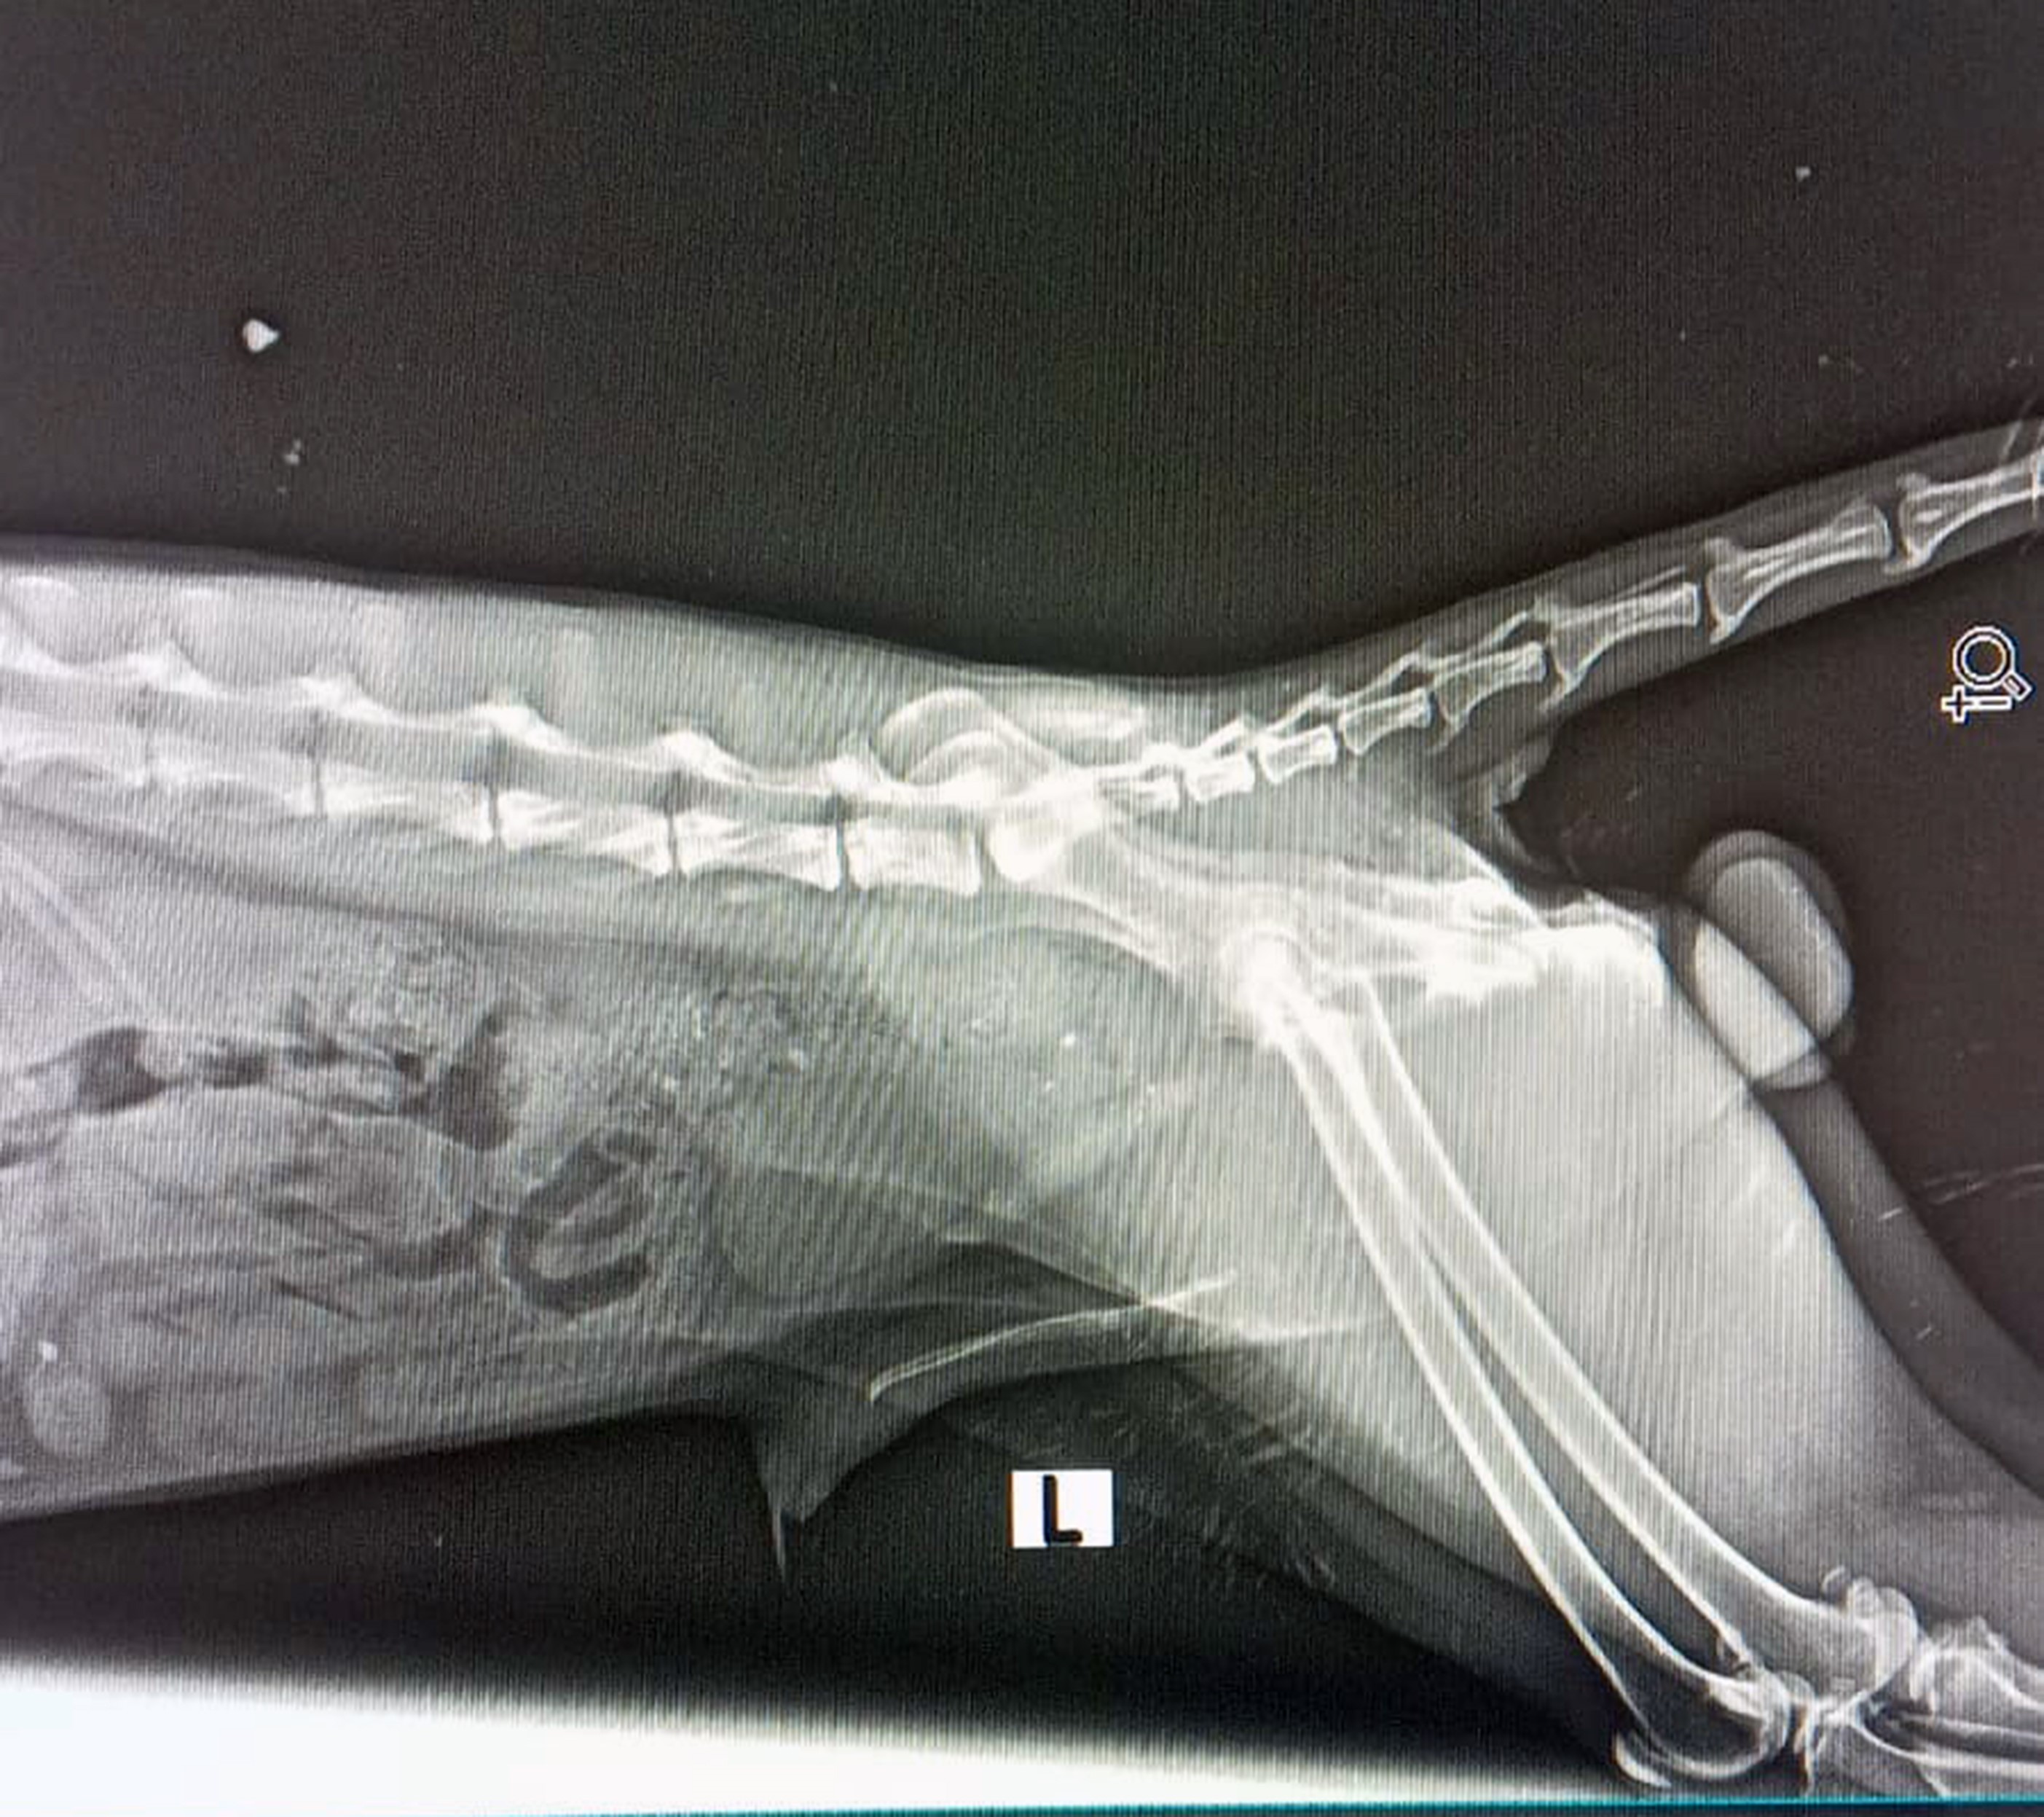

Yaralı tilkinin çekilen filminde arka ayaklarından yaralı olduğu ortaya çıktı. Müşahade altında tutulan Tikinin durumunun stabil hale getirilerek izlendiği açıklandı. Datça DKMP Şefliği, bu sürece katkısı olan tüm gönüllü hayvan severlere teşekkür etti.